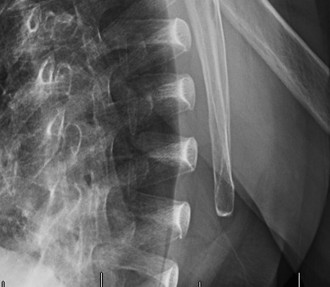

Standard shoulder radiographs (AP, true AP/Grashey, axillary lateral, outlet views) were obtained. These revealed significant findings characteristic of rotator cuff arthropathy (RCA):

* AP View: Marked superior migration of the humeral head with severe narrowing of the acromiohumeral interval, measuring approximately 2mm (normal > 7mm). There was evidence of glenohumeral joint space narrowing, particularly superiorly. Significant osteophyte formation was present around the glenoid rim and humeral head. Scalloping and acetabularization of the undersurface of the acromion and coracoacromial arch were visible, a direct consequence of the chronically superiorly migrated humeral head eroding the arch. Subchondral sclerosis and cystic changes were noted on both the humeral head and glenoid.

* Interpretation of the provided image: This X-ray appears to be an AP view of a shoulder demonstrating classic features of severe rotator cuff arthropathy (Hamada Grade 4 or 5). Key findings include: severe superior migration of the humeral head with obliteration of the acromiohumeral interval, marked glenohumeral joint space narrowing, large superior osteophytes on the glenoid, and acetabularization of the acromion. There is also evidence of cystic changes and sclerosis in the humeral head.

Hamada Classification (Radiographic assessment of RCA):

Based on the plain radiographs, the patient's shoulder demonstrated:

* Grade 1: AC interval > 6 mm.

* Grade 2: AC interval < 6 mm.

* Grade 3: Acetabularization of the acromion.

* Grade 4: Glenohumeral arthritis (4A – no humeral head collapse, 4B – humeral head collapse).

* Grade 5: Humeral head collapse with avascular necrosis (AVN).

Our patient's findings of severe superior migration with an acromiohumeral interval of 2mm, marked acetabularization of the acromion, and significant glenohumeral joint space narrowing with osteophytes and cystic changes, placed him squarely in Hamada Grade 4A (or possibly 4B depending on exact definition of collapse), indicating advanced RCA.